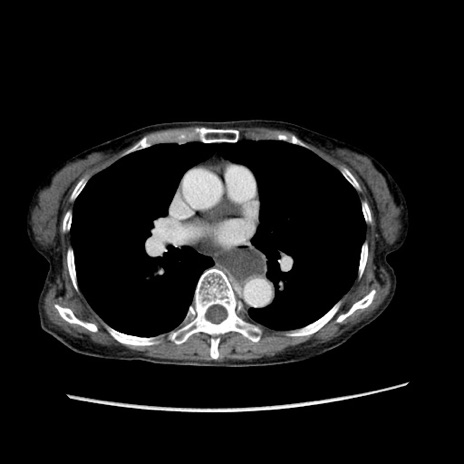

症例25(横断像)

【症例】80歳代女性

【主訴】胸のつかえ感

【現病歴】約9時間前に食後から胸のつかえた感じあり、嘔吐あり、来院。

【既往歴】胃癌(全摘)、胆摘、虫垂炎

【身体所見】心窩部に圧痛あり、反跳痛なし。

【データ】WBC 5700、CRP 0.05